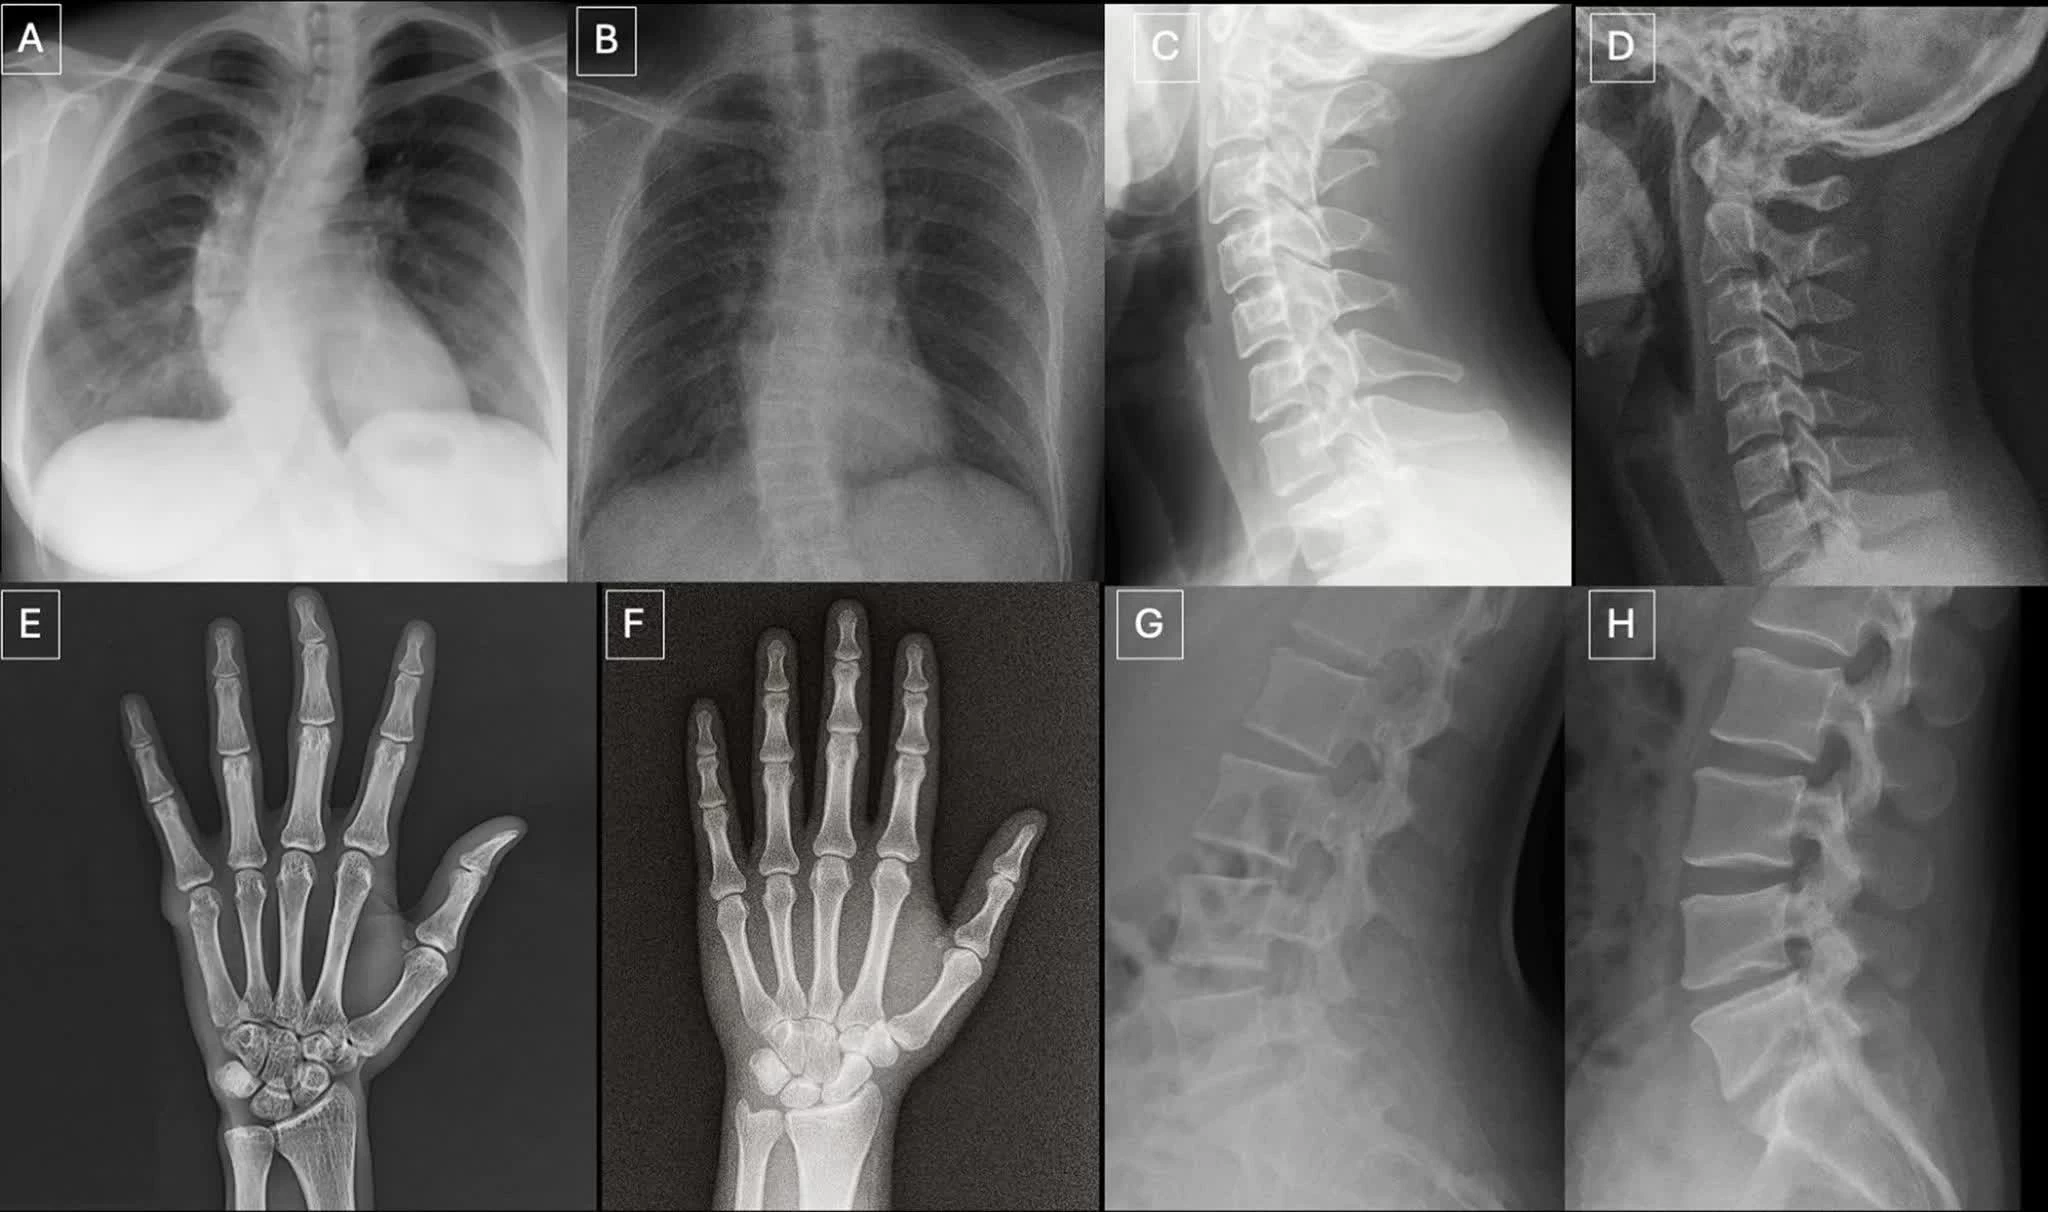

| Ảnh X-quang ghép theo từng cặp gồm ảnh thật và ảnh do GPT-4o tạo ra ở các vị trí khác nhau của cơ thể, cho thấy AI có thể tạo ra hình ảnh y khoa có độ chân thực cao. (Nguồn: RSNA) |

Trong tổng 264 ảnh X-quang được sử dụng trong nghiên cứu, một nửa là ảnh thật và một nửa do AI tạo ra. Các bác sĩ tham gia đánh giá hai bộ dữ liệu riêng biệt, bao gồm nhiều vùng cơ thể và một bộ ảnh X-quang phổi chuyên biệt, được tạo ra bằng các mô hình AI như ChatGPT và RoentGen.

Theo nhóm nghiên cứu, ảnh X-quang giả thường mang một số đặc điểm thị giác tinh vi như cấu trúc xương quá mịn, cột sống thẳng bất thường, phổi đối xứng hoàn hảo, mạch máu phân bố đồng đều và các vết gãy có hình dạng “quá đẹp”, thường chỉ xuất hiện ở một phía của xương.